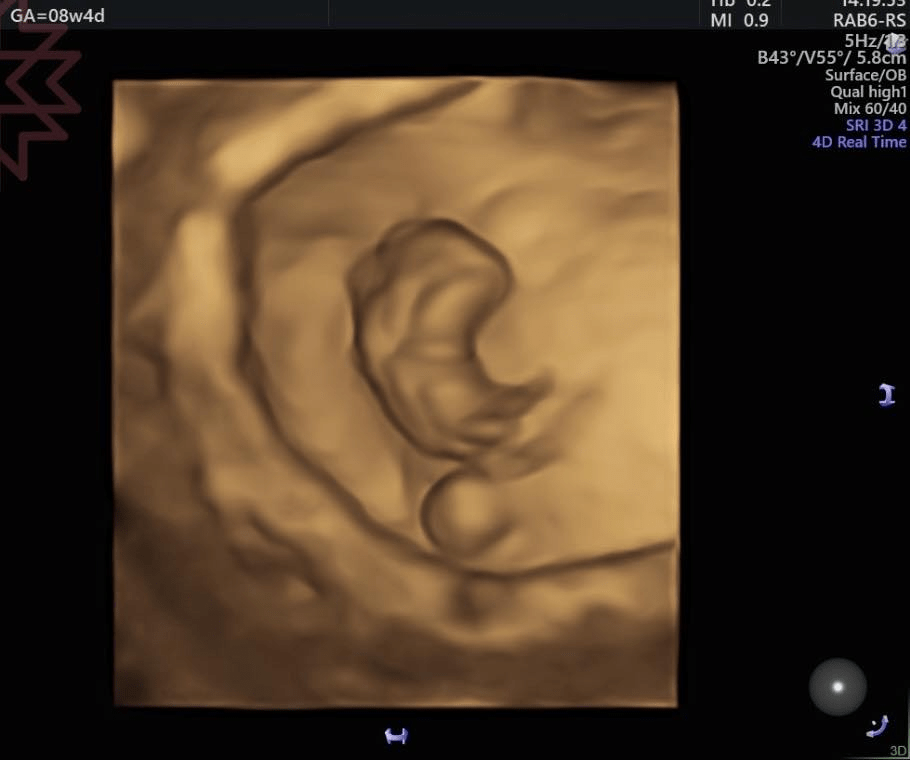

這是八週的立體超音波影像

胎兒下方那顆圓滾滾的小球

就是今天的主角

卵黃囊。

它看起來就像一顆安靜待在旁邊的小珍珠